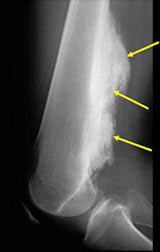

- Large tumors encircle the bone

- Appears to have broad attachment to underlying cortex with a cleft between exophytic base and cortex at periphery. This is referred to as a “String Sign” (cleft is often only identifiable on CT scan)

- There may be invasion of the medullary canal with long standing disease

- High grade or defifferentiated areas may appear as large radiolucent areas/mass adjacent to radiodense areas

- Parosteal osteosarcomas that are present for prolonged periods of time may either have areas that become higher grade or dedifferentiate. Dedifferentiation refers to a portion of the tumor changing and becoming a high grade type of sarcoma. In addition, parosteal osteosarcomas that are present for a prolonged period of time can invade the bone (medullary canal) that it arose from. Tumors that have undergone dedifferentiation or invaded the underlying bone are more aggressive and have a higher risk of metastasizing (spreading). This is important to know for treatment purposes. Typically, low grade parosteal osteosarcomas are treated with surgery alone. Parosteal osteosarcomas with high grade areas may also be treated with chemotherapy in addition to surgery.